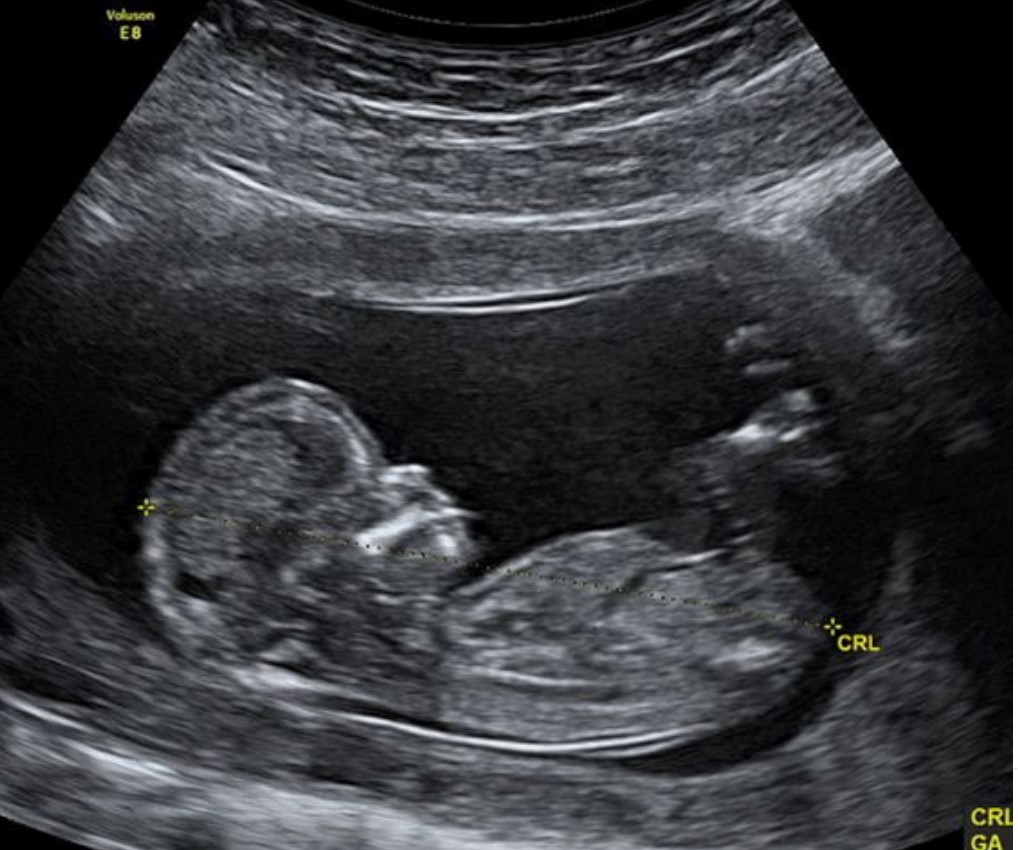

Ecografía de tamizaje genético: aunque puede realizarse entre las semanas 11 a 14, el mejor momento para hacer la ecografía de tamizaje genético es la semana 12. El tamaño actual del bebé permite determinar si la mayoría de órganos se estén desarrollando de manera adecuada. Esta ecografía en manos expertas puede detectar hasta el 60% de las malformaciones mayores que se pueden presentar durante el embarazo.

Uno de los parámetros más importante es la medición de la nuca del bebé conocida como translucencia nucal, que corresponde al líquido que todos los fetos tienen en la parte posterior del cuello. El grosor de la nuca del feto se utiliza para establecer el riesgo de síndrome de Down. Para calcular este riesgo se combina la medida de la nuca con tu edad, la presencia de soplo en el corazón, la forma en que palpita una vena que llega al corazón conocida como ductus venoso y los valores de dos hormonas (BHCG y PAPP-A) que se obtienen mediante una muestra de tu sangre.

Esta ecografía también permite establecer el riesgo de otras posibles complicaciones del embarazo como el parto prematuro, la preeclampsia (presión alta durante el embarazo) y la restricción del crecimiento fetal (bajo peso del bebe durante la gestación). En caso de identificar alto riesgo de preeclampsia tu médico te formulará 150 mg de ácido acetil salicílico cada noche y calcio para disminuir la probabilidad de que esto ocurra.